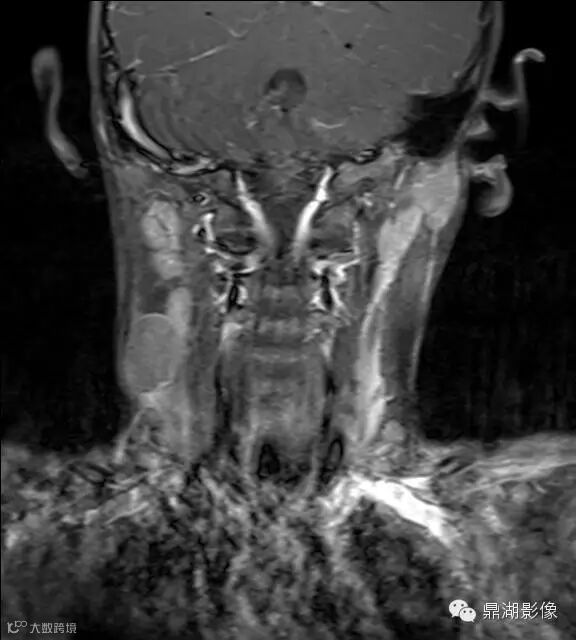

病史:男,5岁,发烧起病 39.5,咽痛,扁桃体II度,家属发现颈部肿块,质地硬,压痛。

上海儿童医院韩燕乔教授诊断:考虑淋巴结炎 ,可见杯状分层,液液平

出院临床诊断:上呼吸道支原体感染,淋巴结炎

颌面部淋巴结炎是临床较常见的一种疾病,尤其是小孩发病率更高。经常发生在颌下及颏下,有时也发生在耳后,面部和颈侧。颌面部的淋巴结炎大多是以下原因引起感染。上呼吸道感染,如扁桃体炎、咽炎、鼻炎、鼻窦炎等;口腔感染,如牙龈炎、牙周炎、口腔溃疡、冠周炎等;皮肤损伤与感染,如头面部皮肤化脓性伤口、湿疹感染、疖肿等。以上各种感染的细菌均可以随着淋巴液的循环,流经颌面部的相应淋巴结,使相应部位的淋巴结遭受细菌的侵犯,引起淋巴结的炎症。